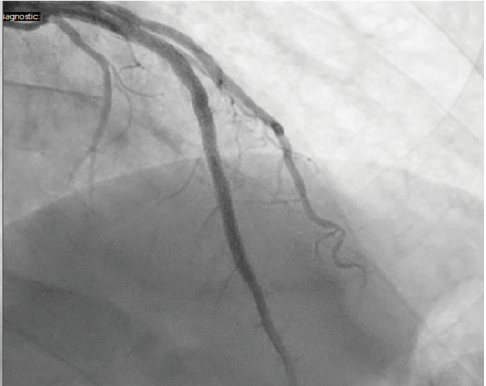

Case 3: LAD CTO Requiring Lesion Preparation With Takeru™ and Adjunctive IVL

A 54-year-old male with a history of chronic smoking and a known chronic total occlusion of the left anterior descending (LAD) artery presented with recurrent angina. Stress testing revealed a reversible perfusion defect in the anterior and apical segments. The patient was scheduled for elective CTO PCI. Right femoral access was obtained, and an 8 Fr sheath was inserted. The left coronary artery was engaged with an EBU 4.0 guide catheter with an initial angiogram showing a CTO of the proximal LAD with distal filling from left-to-left collaterals (Figure 7).